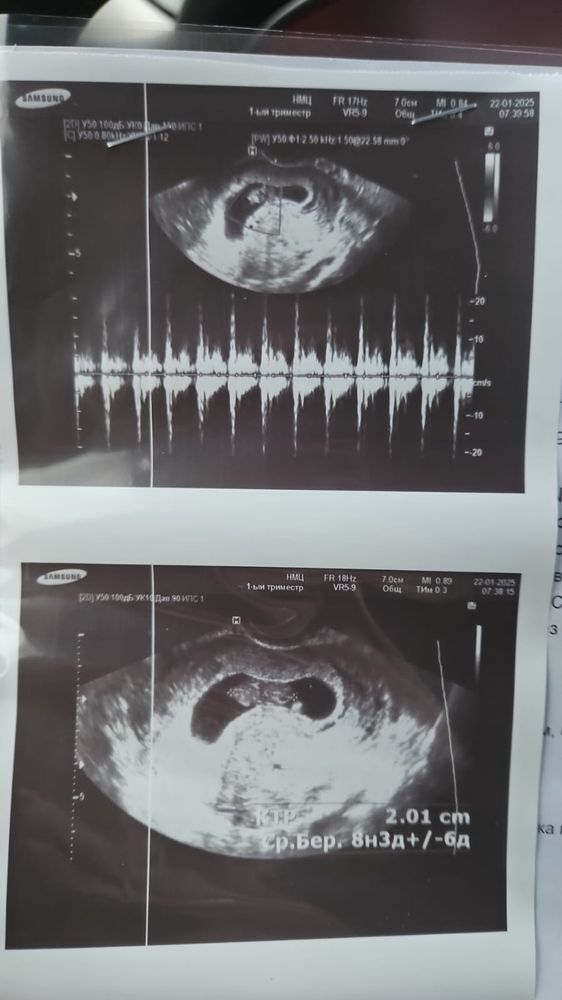

УЗИ 9 недель, тонус